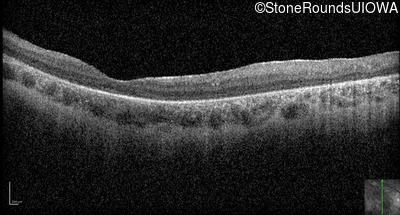

Optical Coherence Tomography - Right - 10/300 sc

Exemplar / OCT Stack